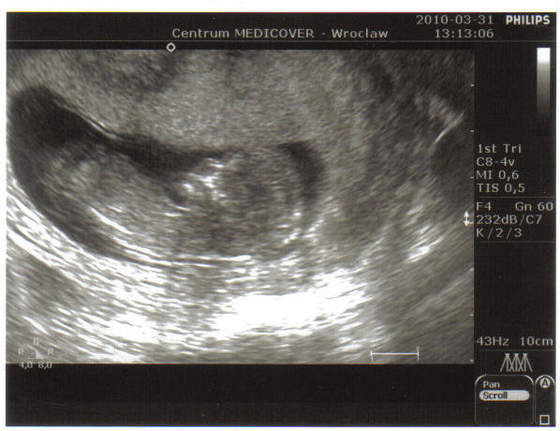

Zdjęcia fasolek

a to moj maluszek w 12 tygodniu :-)

Załączniki

• img013..jpg

img013..jpg

19,8 KB · Wyświetleń: 117